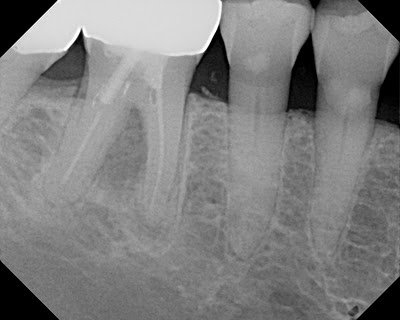

At 18 months, the lesion continues to improve, tooth is completely asymptomatic and functional. Proper endodontic treatment and repair with MTA has retained a tooth that many would have considered “hopeless” or non-restorable based on the amount of furcal bone loss.